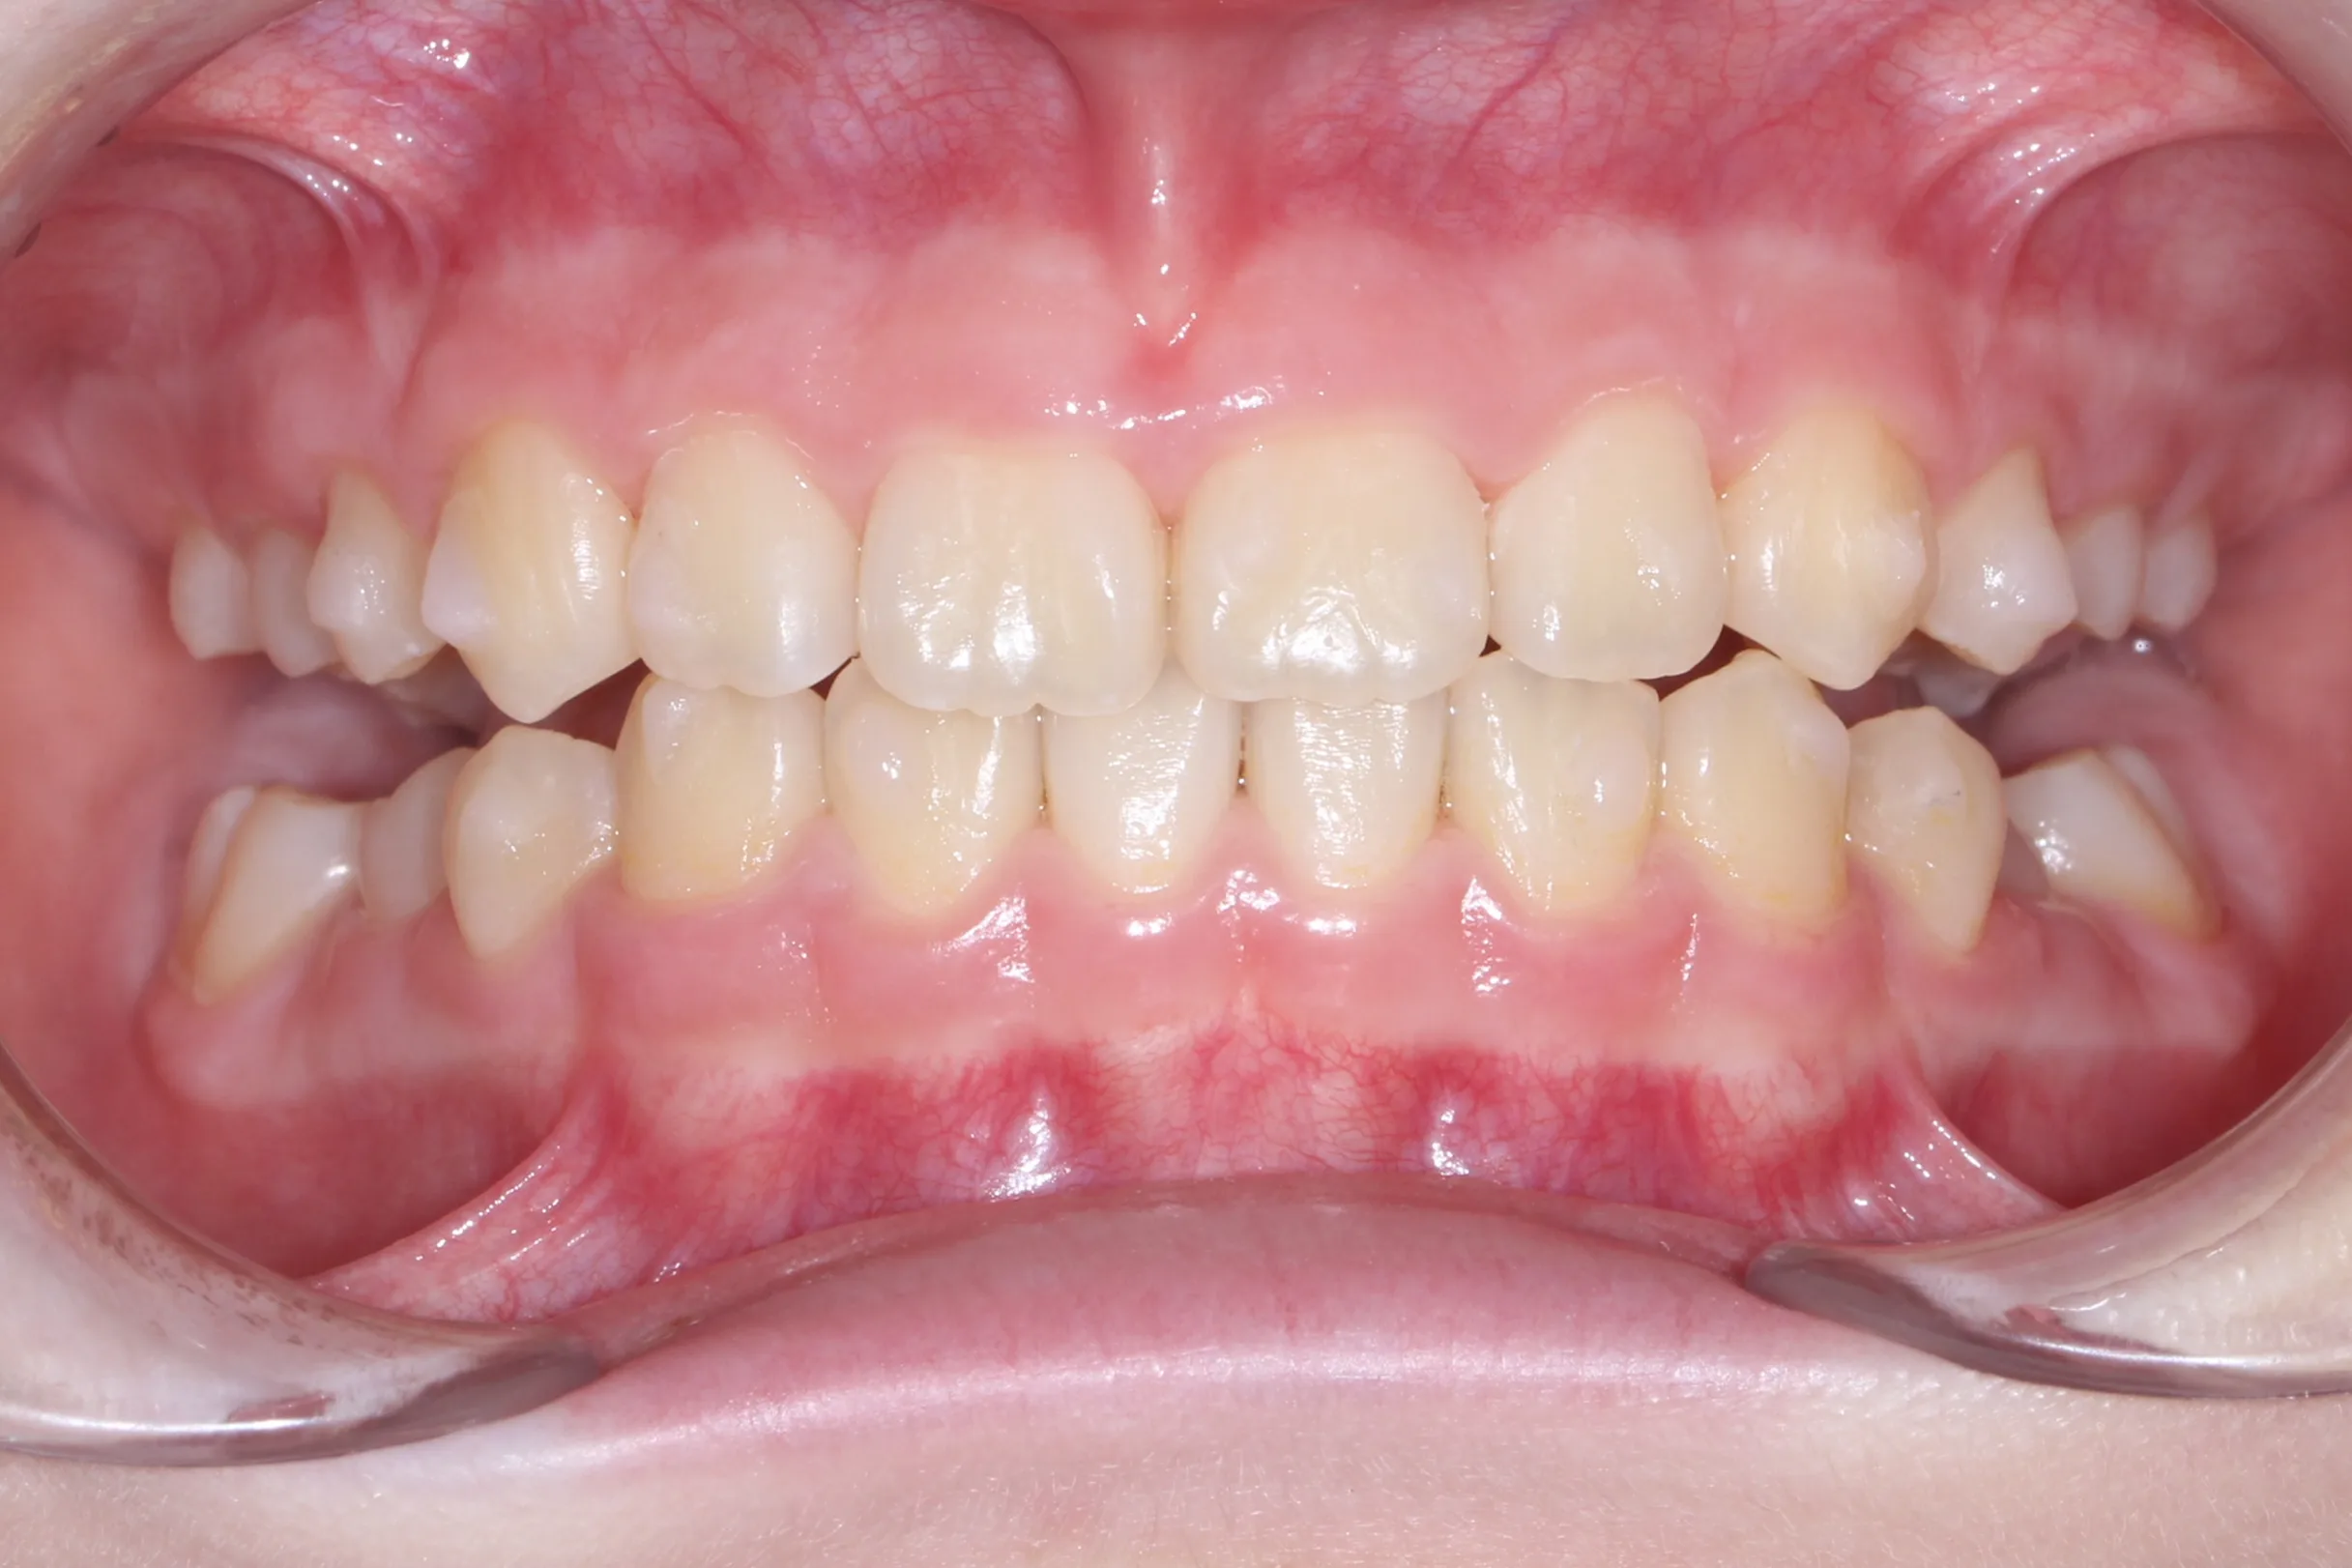

만 11세 환자분께서 튀어나온 앞니와 다물어지지 않는 입술 때문에 내원하셨습니다. 검진 결과 상악 전돌을 동반한 2급 부정교합(Class II malocclusion) 상태였으며, 아래턱의 성장이 다소 부족하여 골격적인 조화가 필요한 상황이었습니다.

이번 치료에는 인비절라인 퍼스트(Invisalign First)에 하악 전방 견인(Mandibular Advancement, MA wing)을 추가하여 치료를 진행하였습니다. 성장기라는 시기적 특성을 적극 활용하여 아래턱의 점진적인 성장을 유도하고, 과도한 상악 전치부 돌출을 개선하는 데 치료의 핵심 전략을 두었습니다.

2년 7개월의 치료 과정을 거치며 환자분의 협조도 덕분에 안모 프로파일과 교합이 안정적으로 개선되었습니다. 성장기라고 해서 무조건 교정이 어려운 것은 아닙니다. 적절한 시기에 맞춤형 장치를 선택한다면 골격적 불균형을 효과적으로 바로잡을 수 있습니다.